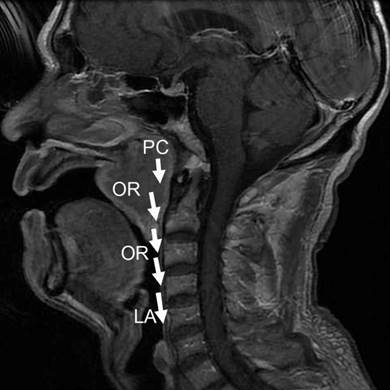

Figure 7

The second new model for regional invasion of NACC. This route was pharyngonasal cavity (PC) → oropharynx (OR) → laryngopharynx (LA), as shown with white arrows.